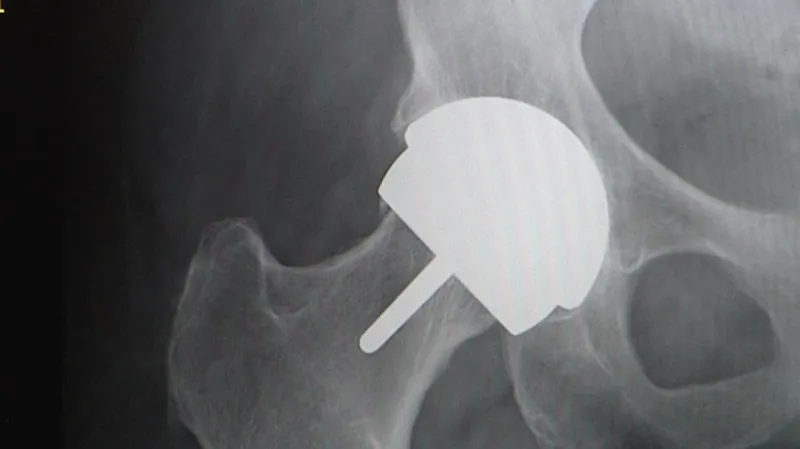

Deník zveřejnil sérii reportáží, kdy v jedné z nich jeho reportéři vydávající se za čínského výrobce nabízeli fiktivní umělý kyčelní kloub. Byl založen na produktu společnosti DePuy, která ho musela v celém světě stáhnout kvůli tomu, že se rychle opotřebovává a dostávají se z něj do krve potenciálně jedovaté látky. Tento kloub DePuy ASR XL Acetabular System se v Británii již nesmí používat.